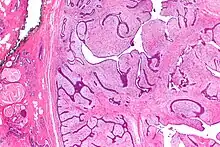

| Micrograph of a phyllodes tumor (right of image) with the characteristic long clefts and myxoid cellular stroma. Normal breast and fibrocystic change are also seen (left of image). H&E stain. |